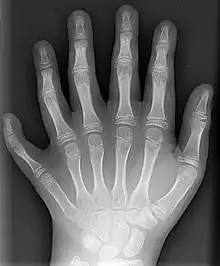

A radiography of the left hand of a person with polydactyly

1. (teratology) A condition in which a person or animal has more than the usual number of digits (fingers or toes) on at least one of their hands or feet.